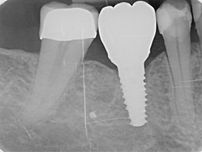

STRAUMANN® iEXCEL | CLINICAL CASE

LOWER MOLAR TOOTH REPLACEMENT IN HEALED SITE

Freehand surgery for a lower molar tooth replacement in a healed site using an apically tapered Straumann® BLC implant ∅ 4.5 mm x 12 mm SLActive®, Roxolid®, and following a conventional loading protocol.

Dr. Algirdas Puišys